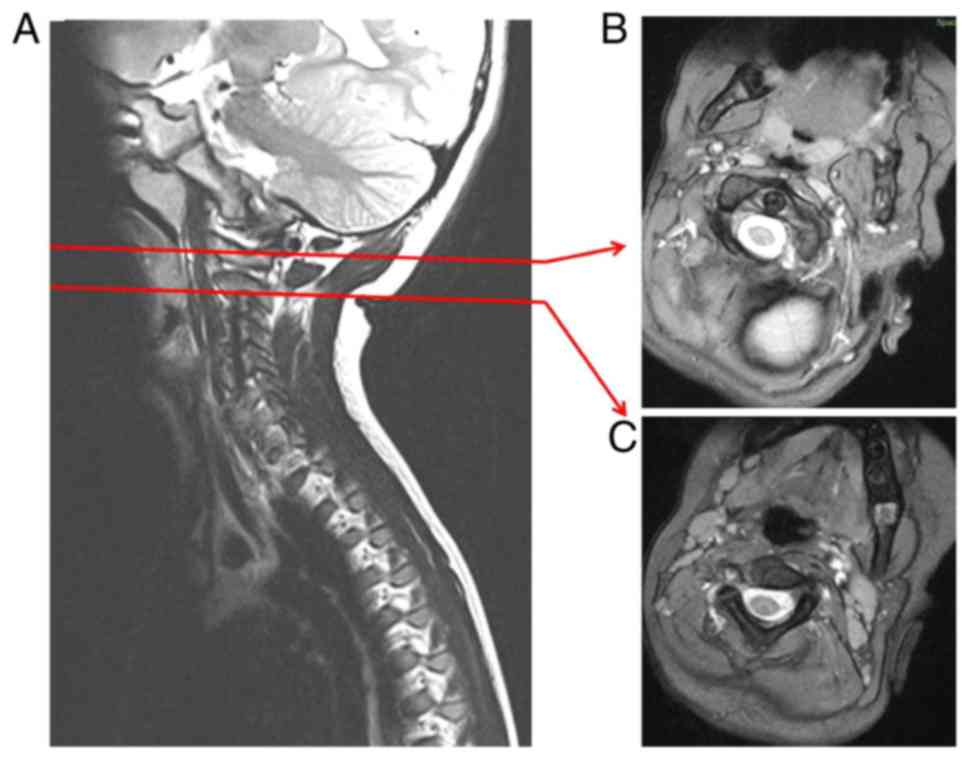

Atlantoaxial Joint Subluxation

Atlantoaxial Subluxation - Musculoskeletal and Connective Tissue Disorders - Merck Manuals Professional Edition Atlanto-axial subluxation | Radiology Reference Article | Radiopaedia.org Atlantoaxial Instability (Atlantoaxial Subluxation): Practice Essentials, Background, Epidemiology Atlantoaxial Instability - Spine - Orthobullets Diagnosis and Treatment of Atlantoaxial Dislocation & Atlantoaxial Subluxation in India | Dr Sumit Sinha Atlantoaxial Joint Subluxation